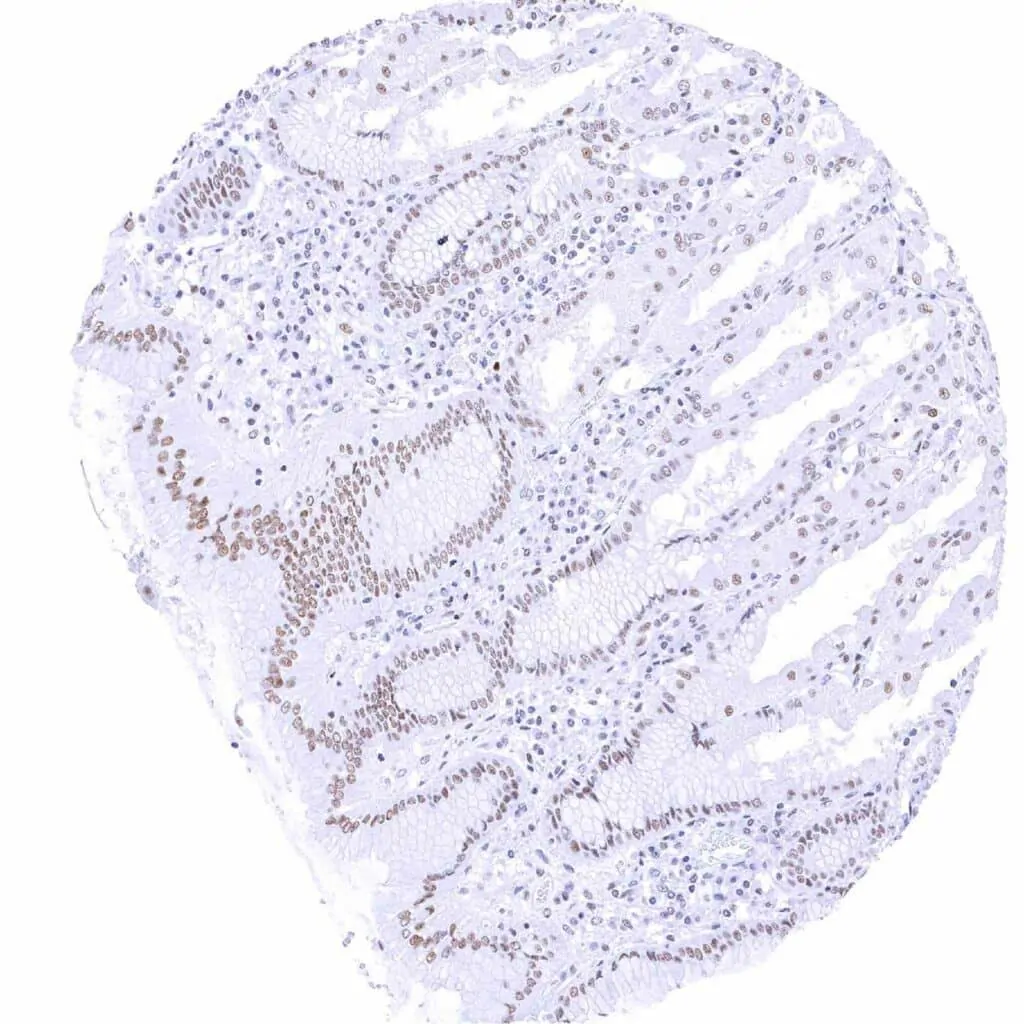

Colon descendens, mucosa – Weak to moderate TLE1 staining in epithelial cells. Staining is stronger in crypts than at the surface